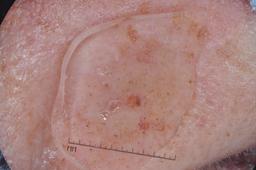

ISIC-DICM-17K (ISIC Dermoscopic Images and Clinical Metadata 17K) is a curated and balanced dataset derived from the International Skin Imaging Collaboration (ISIC) Archive Gallery. It comprises 17,060 dermoscopic images and clinical metadata (8,530 melanoma and 8,530 non-melanoma classes).

For more details, please follow the project’s GitHub repository: https://github.com/mmu-dermatology-research/isic-dicm-17k

This dataset was used in this study and benchmark to explore the effectiveness of multimodal learning for skin lesion classification:

S. Ahammed, X. Cui, W. Lu and M. H. Yap, "Skin Lesion Classification using Dermoscopic Images and Clinical Metadata: Insights from Multimodal Models," 2025 IEEE/CVF Conference on Computer Vision and Pattern Recognition Workshops (CVPRW), Nashville, TN, USA, 2025, pp. 222-230, DOI: 10.1109/CVPRW67362.2025.00027